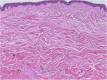

There has been a long-standing need for guidelines on the diagnosis and treatment of keloids and hypertrophic scars that are based on an understanding of the pathomechanisms that underlie these skin fibrotic diseases. This is particularly true for clinicians who deal with Asian and African patients because these ethnicities are highly prone to these diseases. By contrast, Caucasians are less likely to develop keloids and hypertrophic scars, and if they do, the scars tend not to be severe. This ethnic disparity also means that countries vary in terms of their differential diagnostic algorithms. The lack of clear treatment guidelines also means that primary care physicians are currently applying a hotchpotch of treatments, with uneven outcomes. To overcome these issues, the Japan Scar Workshop (JSW) has created a tool that allows clinicians to objectively diagnose and distinguish between keloids, hypertrophic scars, and mature scars. This tool is called the JSW Scar Scale (JSS) and it involves scoring the risk factors of the individual patients and the affected areas. The tool is simple and easy to use. As a result, even physicians who are not accustomed to keloids and hypertrophic scars can easily diagnose them and judge their severity. The JSW has also established a committee that, in cooperation with outside experts in various fields, has prepared a Consensus Document on keloid and hypertrophic scar treatment guidelines. These guidelines are simple and will allow even inexperienced clinicians to choose the most appropriate treatment strategy. The Consensus Document is provided in this article. It describes (1) the diagnostic algorithm for pathological scars and how to differentiate them from clinically similar benign and malignant tumors, (2) the general treatment algorithms for keloids and hypertrophic scars at different medical facilities, (3) the rationale behind each treatment for keloids and hypertrophic scars, and (4) the body site-specific treatment protocols for these scars. We believe that this Consensus Document will be helpful for physicians from all over the world who treat keloids and hypertrophic scars.